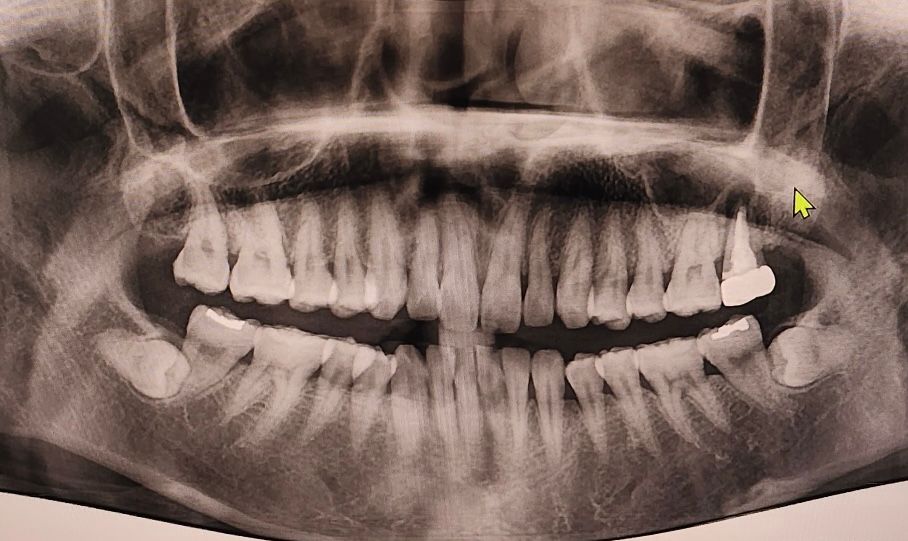

상악동 거상술은 임플란트 심을 떄 남은 뼈가 부족하여 상악동을 말 그대로 거상한 후 골이식을 하는 것을 말합니다. 지금 x ray 사진으로 보기에는 상악동 까지의 뼈가 어느 정도 있는 편이라 상악동거상술 안해도 될 것으로 보입니다.

왼쪽위 젤 뒤에 치아끝에 염증이 많으신거 같습니다. 발치를 하고 3개월정도 기다리셧다가 잇몸뼈가 많이 안차면 그떄 상악동 거상술을 하셔야될것같습니다.